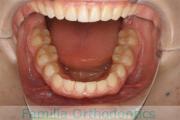

- ≫治療前

-

下の親知らずを抜歯してから、その部位にアンカースクリューを埋入して、下の歯並びを後ろに引っぱりながら、さらに小臼歯も抜歯しました。

上顎

下顎

- ≫治療後

3年半、40回の通院が必要でしたが、とてもよくなりました。

ただ開咬も叢生を後戻りのリスクが高いため、今後の保定観察と舌の癖の訓練がとても大切です。